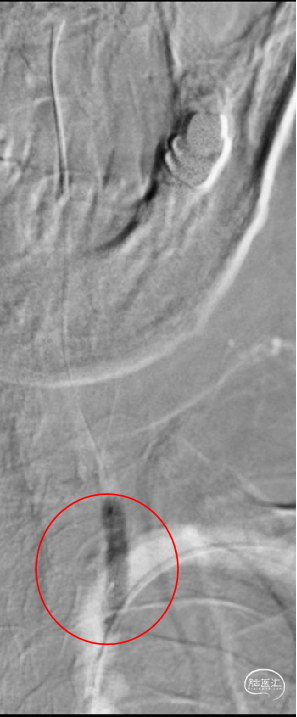

患者左侧椎动脉稍优势,右侧椎动脉开口重度狭窄、次全闭塞,左椎开口重度狭窄。

置入0.018inch*300cm微导丝至左锁骨下远端,以0.014inch*200cm微导丝携带0.017inch微导管进入左侧椎动脉V2段,微量造影确认位于血管真腔。通过0.014inch*300cm微导丝交换技术,将2.0mm*20mm球囊扩张导管置入左侧椎动脉V1狭窄段。

2.0mm*20mm球囊扩张导管置入左侧椎动脉V1狭窄段,造影确认后予以10 atm预扩张;球囊扩张后患者狭窄较前改善。

患者左侧锁骨下动脉重度狭窄伴斑块形成,左侧椎动脉开口处次全闭塞,右侧椎动脉开口处中重度狭窄,右侧后交通动脉发达。

置入0.018inch*300cm微导丝至锁骨下远端,以0.014inch*200cm微导丝携带0.017inch微导管通过狭窄段,置入V2段,微量造影确认位于血管真腔,以0.014inch*300cm微导丝行长导丝交换技术将2.0mm×20mm球囊扩张导管部分送至左侧椎动脉狭窄段。

将2.0mm×20mm球囊扩张导管部分送至左侧椎动脉狭窄段,造影确认后,以8 atm行预扩张,患者无不适,回撤球囊、复查造影,提示狭窄程度部分改善。